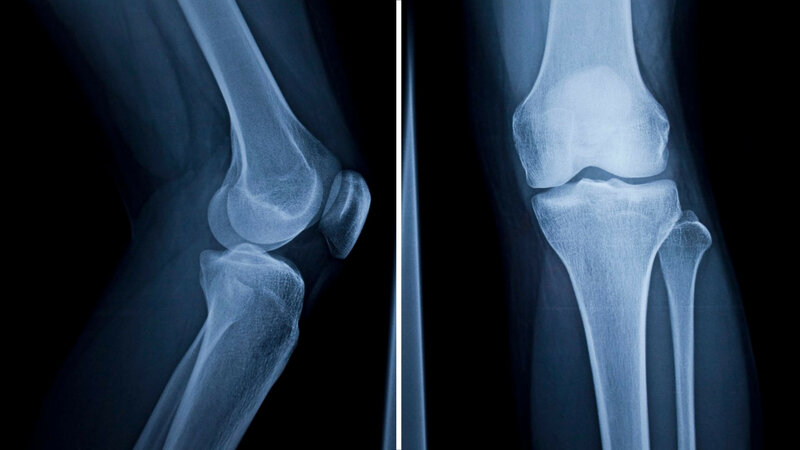

A small tweak to genes may finally enable us to regrow cartilage